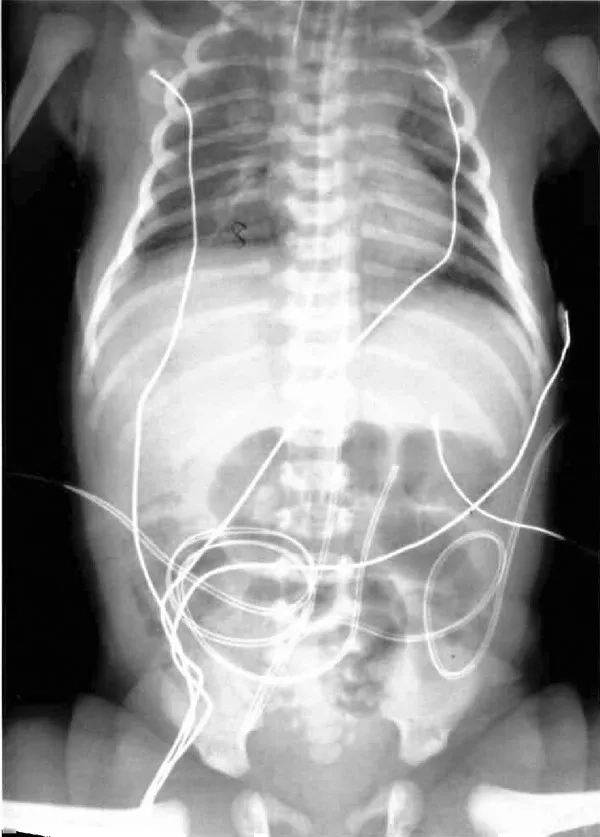

Pneumococcal disease in humans image